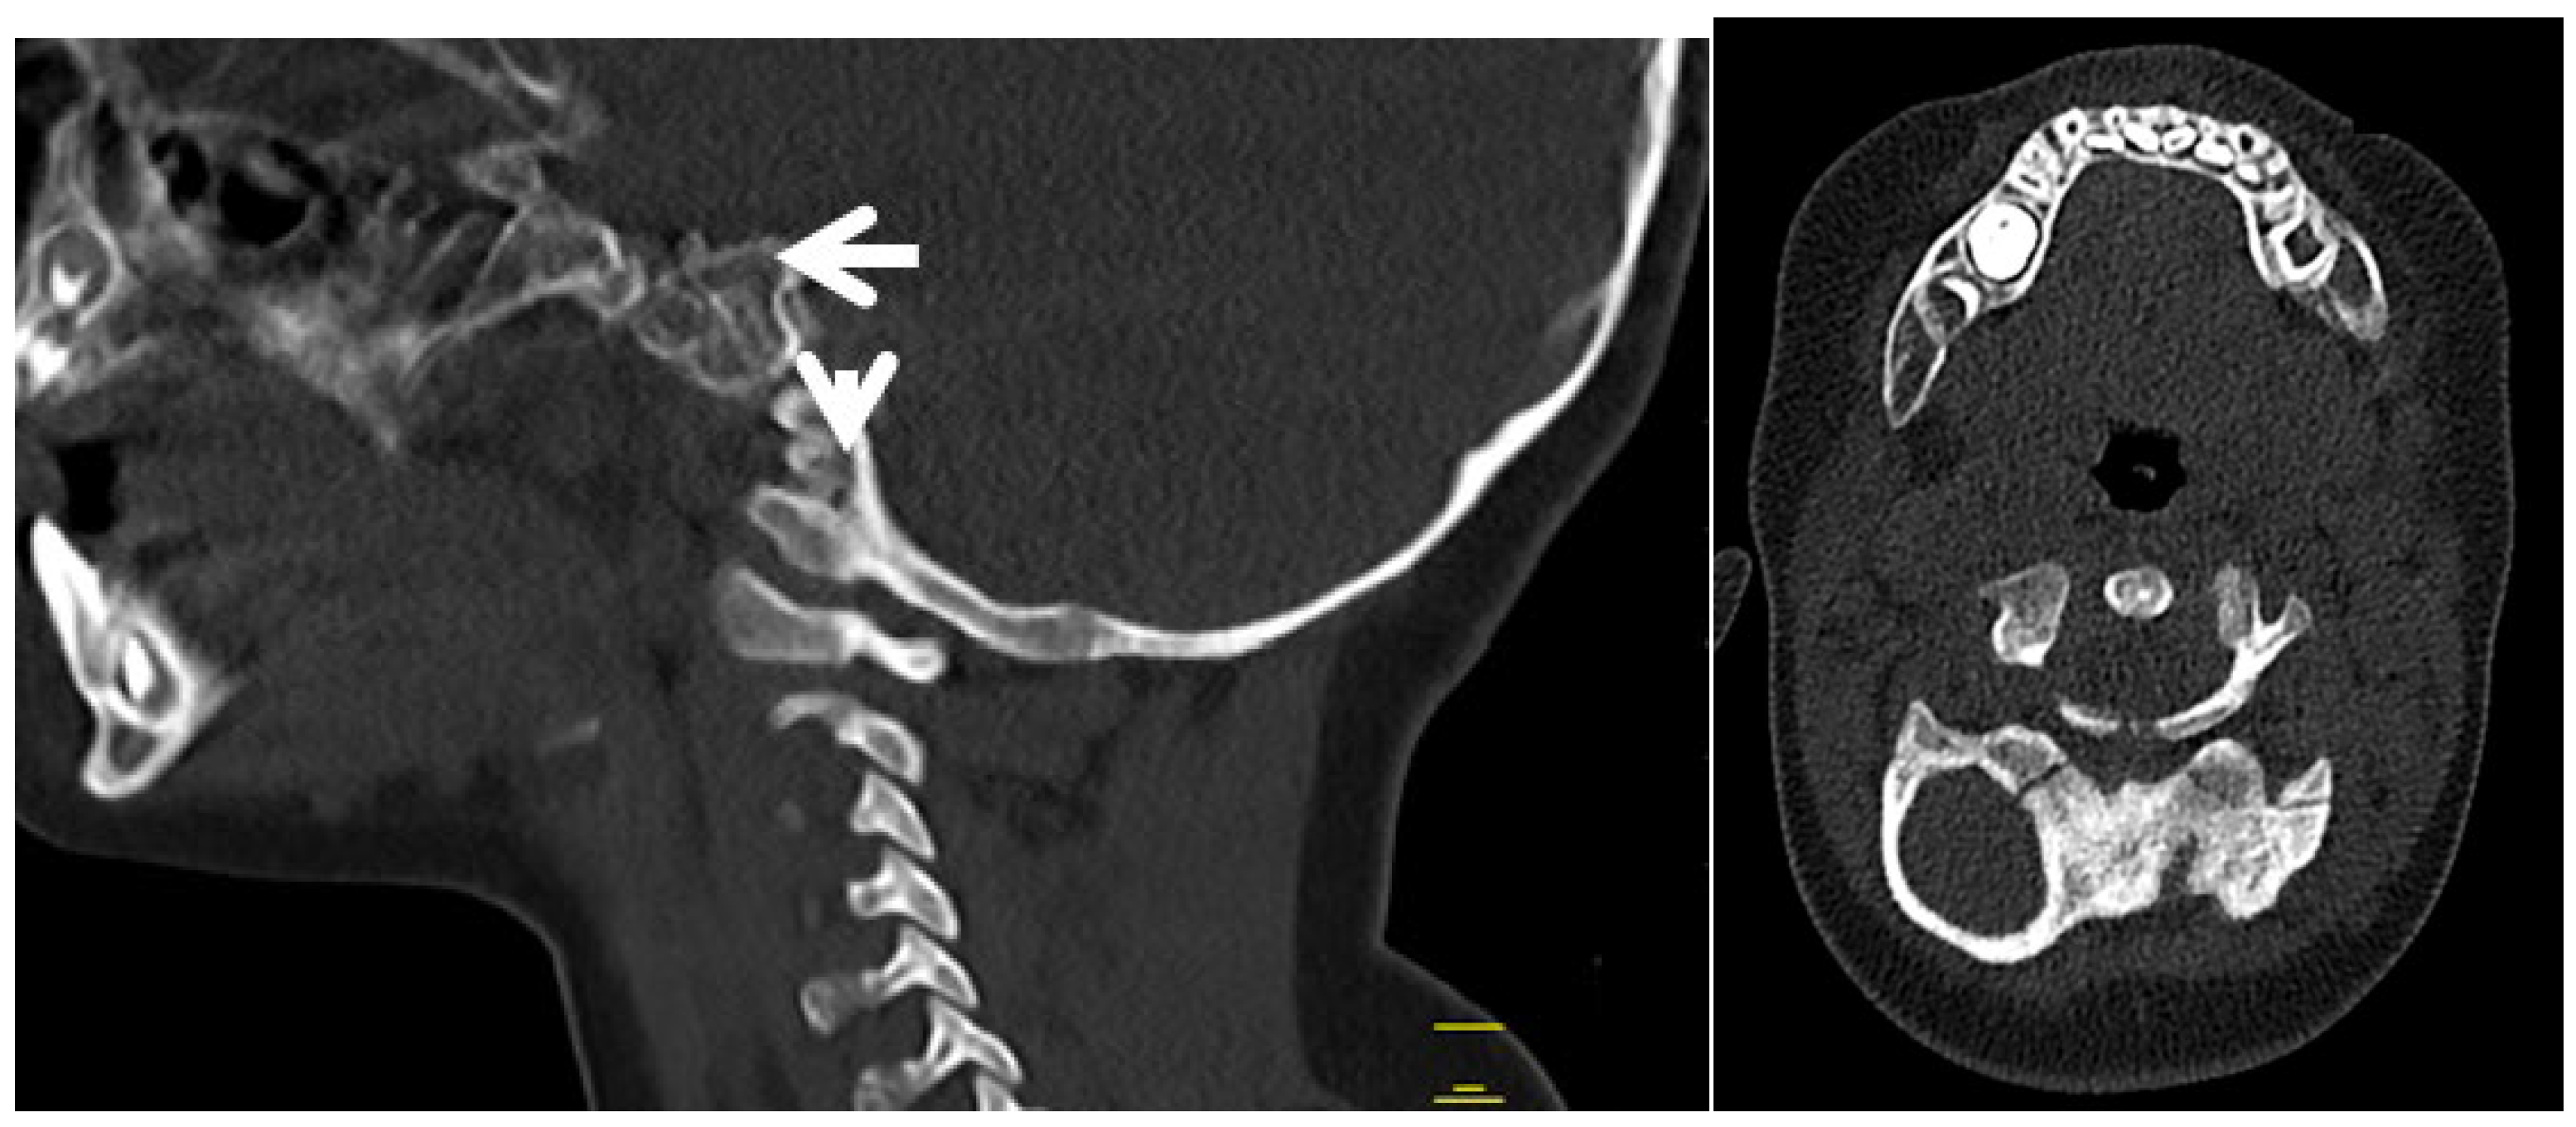

3.2. Congenital Tetraplegia in A Child with Larsen Syndrome